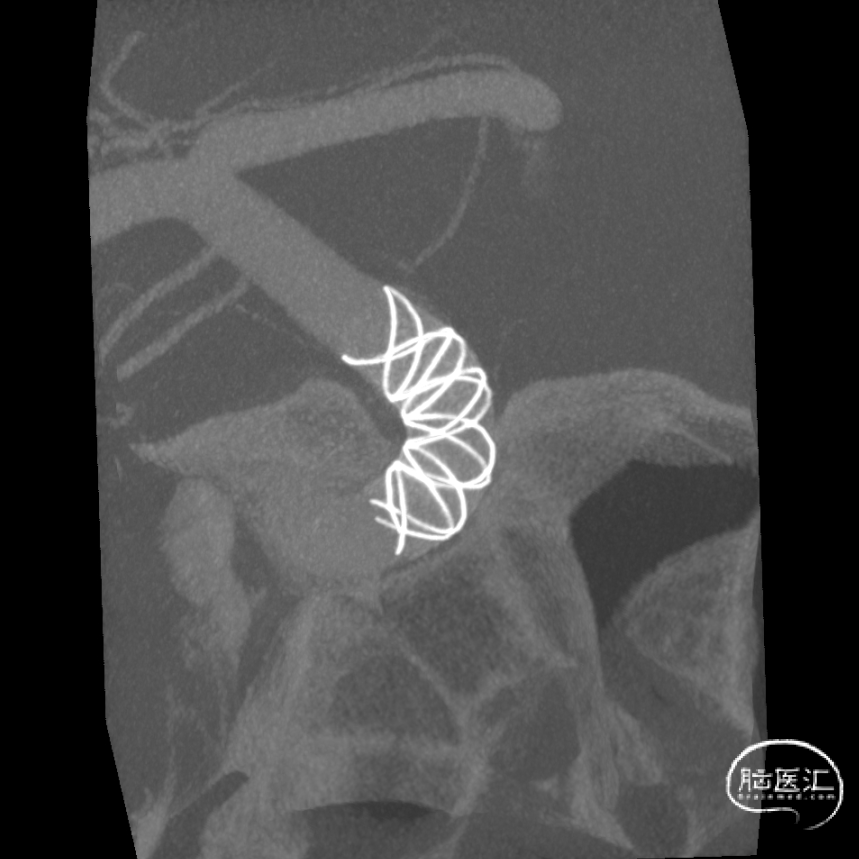

术后支架显影:

术后支架显影:定位精准,未覆盖颞前动脉及大脑前动脉。